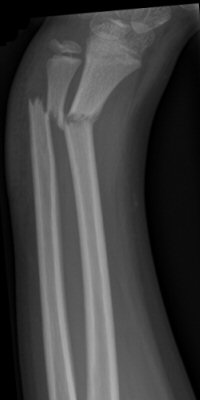

Distala diafysära radius- och ulnafrakturer, opererade med TEN-spikar, sista bilderna läkt efter 7 månader. Alla bilderna är från samma patient.